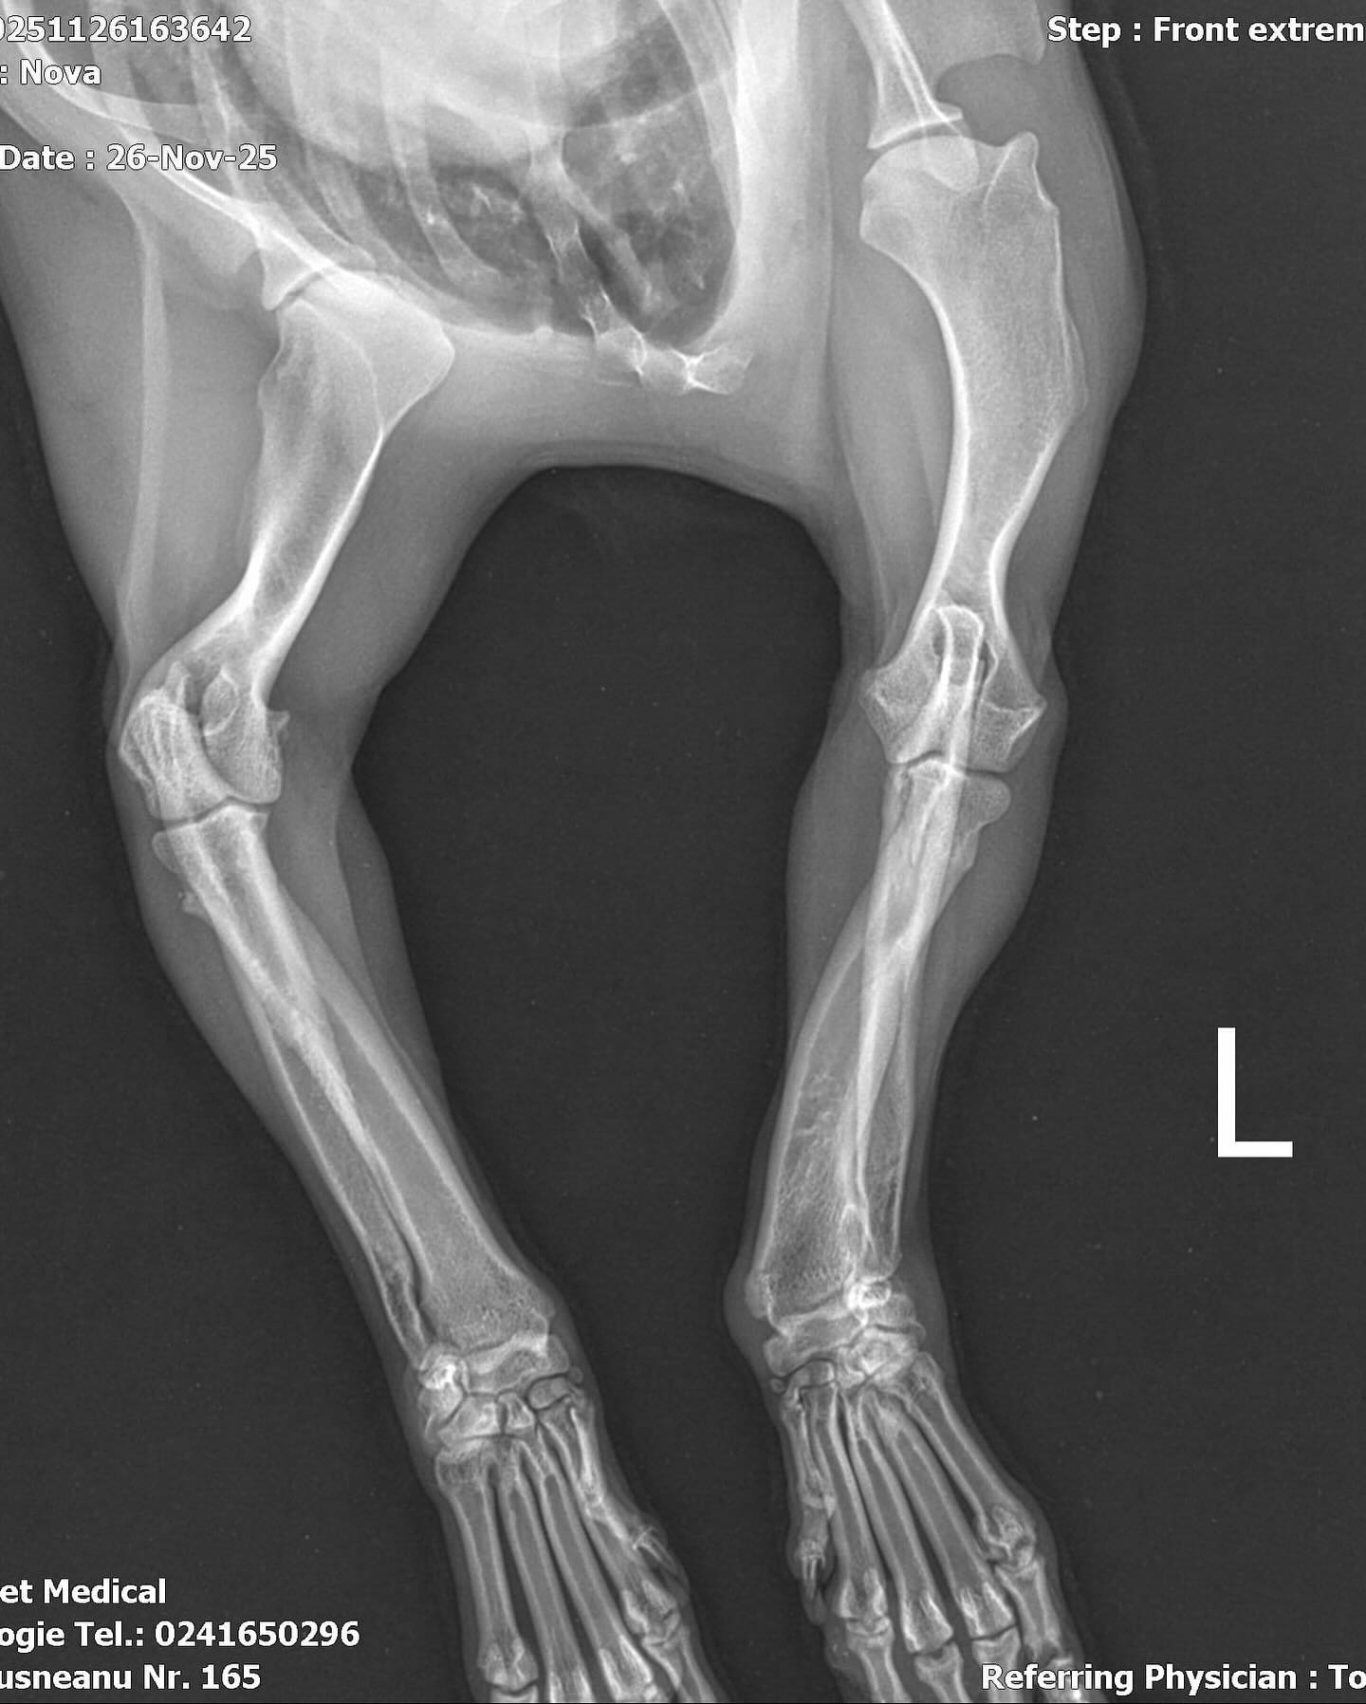

Bei der Untersuchung wurde festgestellt, dass Nova an der Pfote operiert werden muss, damit sie irgendwann schmerzfrei und normal laufen kann.